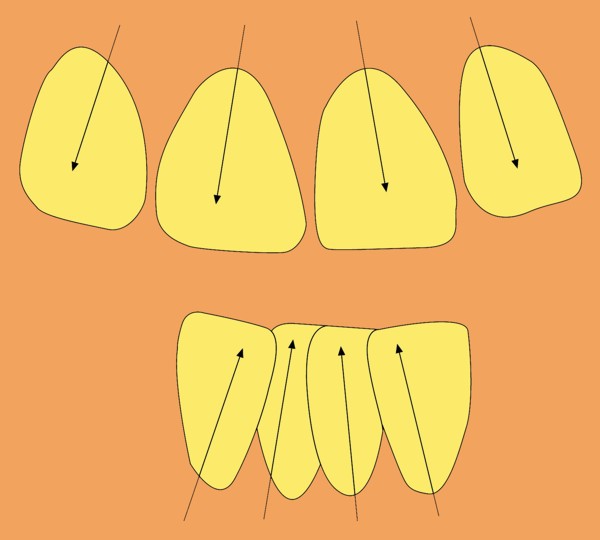

Este artículo pertenece a la categoría: Casos Clínicos

Sin embargo, otras fuerzas que provienen de la parafunción como a veces de la función misma, generan fracturas que hacen de dichas fuerzas, una auténtica etiopatogenia que no debemos pasar por alto, ya que nos conducen indefectiblemente a la génesis de muchos problemas.

Dicho trabajo protético, había sido montado en Oclusión Habitual, tal como se realizan la mayoría de los trabajos individuales, debido a que no todos los pacientes toleran la realización de un Ajuste Oclusal, por tener que intervenir en zonas alejadas a la pieza en cuestión.

Fig.04(Pie de foto: Oclusión Habitual

Fig.05(Pie de foto: Oclusión en Relación Céntrica)

Fig.06(Pie de foto: Faceta mesial superior)

Fig.07(Pie de foto: faceta distal inferior)

Fig.08(Pie de foto: Plano inclinado generador de la discrepancia)

Con una Oclusión Mutuamente Compartida lograda mediante un simple Ajuste Oclusal por sustracción en sus Puntos Prematuros, y por adición en sus contactos caninos, realizados por supuesto previamente a la implantación.

Fig .38(Pié de foto: Punto Prematuro de Contacto)

Fig.39(Pie de foto: Dispersión y Apiñamiento)